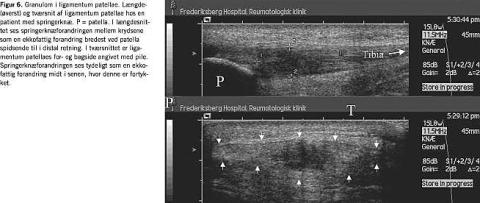

Senernes struktur skal ved UL-undersøgelse vurderes i både tvær- og længdesnit. Ved mistanke om inflammation og/eller skader i de store sener f.eks. akilles- og quadricepssenerne fokuseres der på forekomst af granulomdannelse og hel eller partiel ruptur (Fig. 6 og Fig. 7 ).

Inflammation omkring sener ved tenosynovit fremstår på gråtonebilledet som en relativt ekkofattig struktur med uregelmæssigt fordelt synovialisvæv og områder med væskeansamling. En påvisning af disse forandringer kan lede direkte over i behandling, og på Fig. 8 ses en tenosynovit med nål placeret i seneskeden lige over selve senen. I mere kroniske tilfælde forekommer der i seneskeder ofte ekkoer fra vævsrester, der ligesom ganglier kan give et meget uensartet skanningsbillede. I skulderen kan kalkansamling, defekter eller ruptur i supraspinatussenen diagnosticeres.